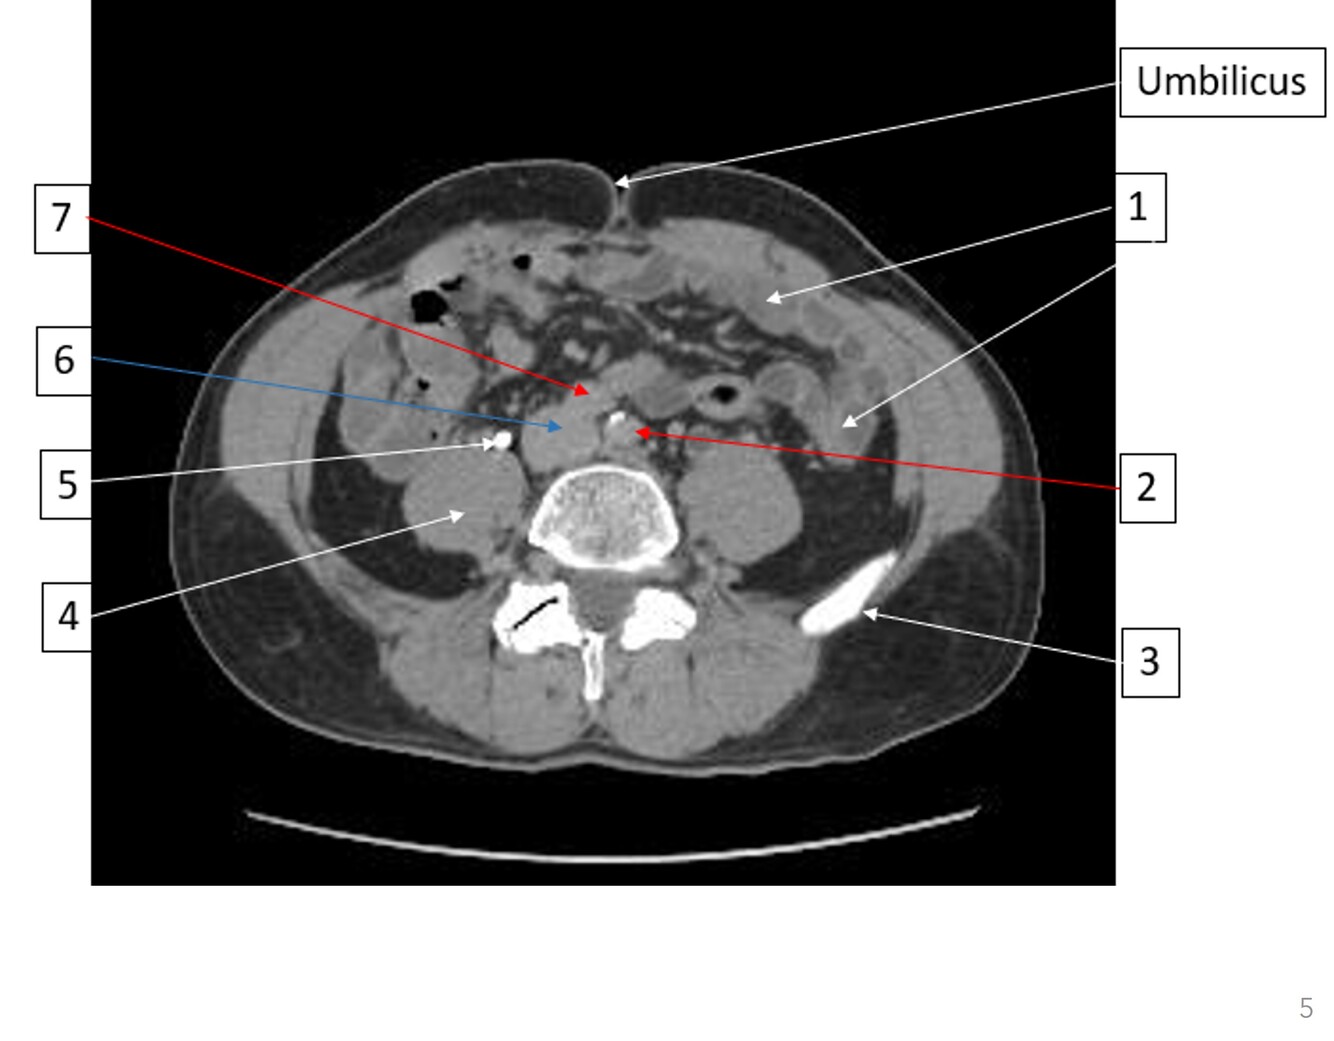

4

Q

Label 1-7

A

1. Small bowel

2. Lt common iliac artery

3. Lt iliac crest

4. Rt psoas

5. Rt ureter

6. IVC

7. Rt common iliac artery

How well did you know this?